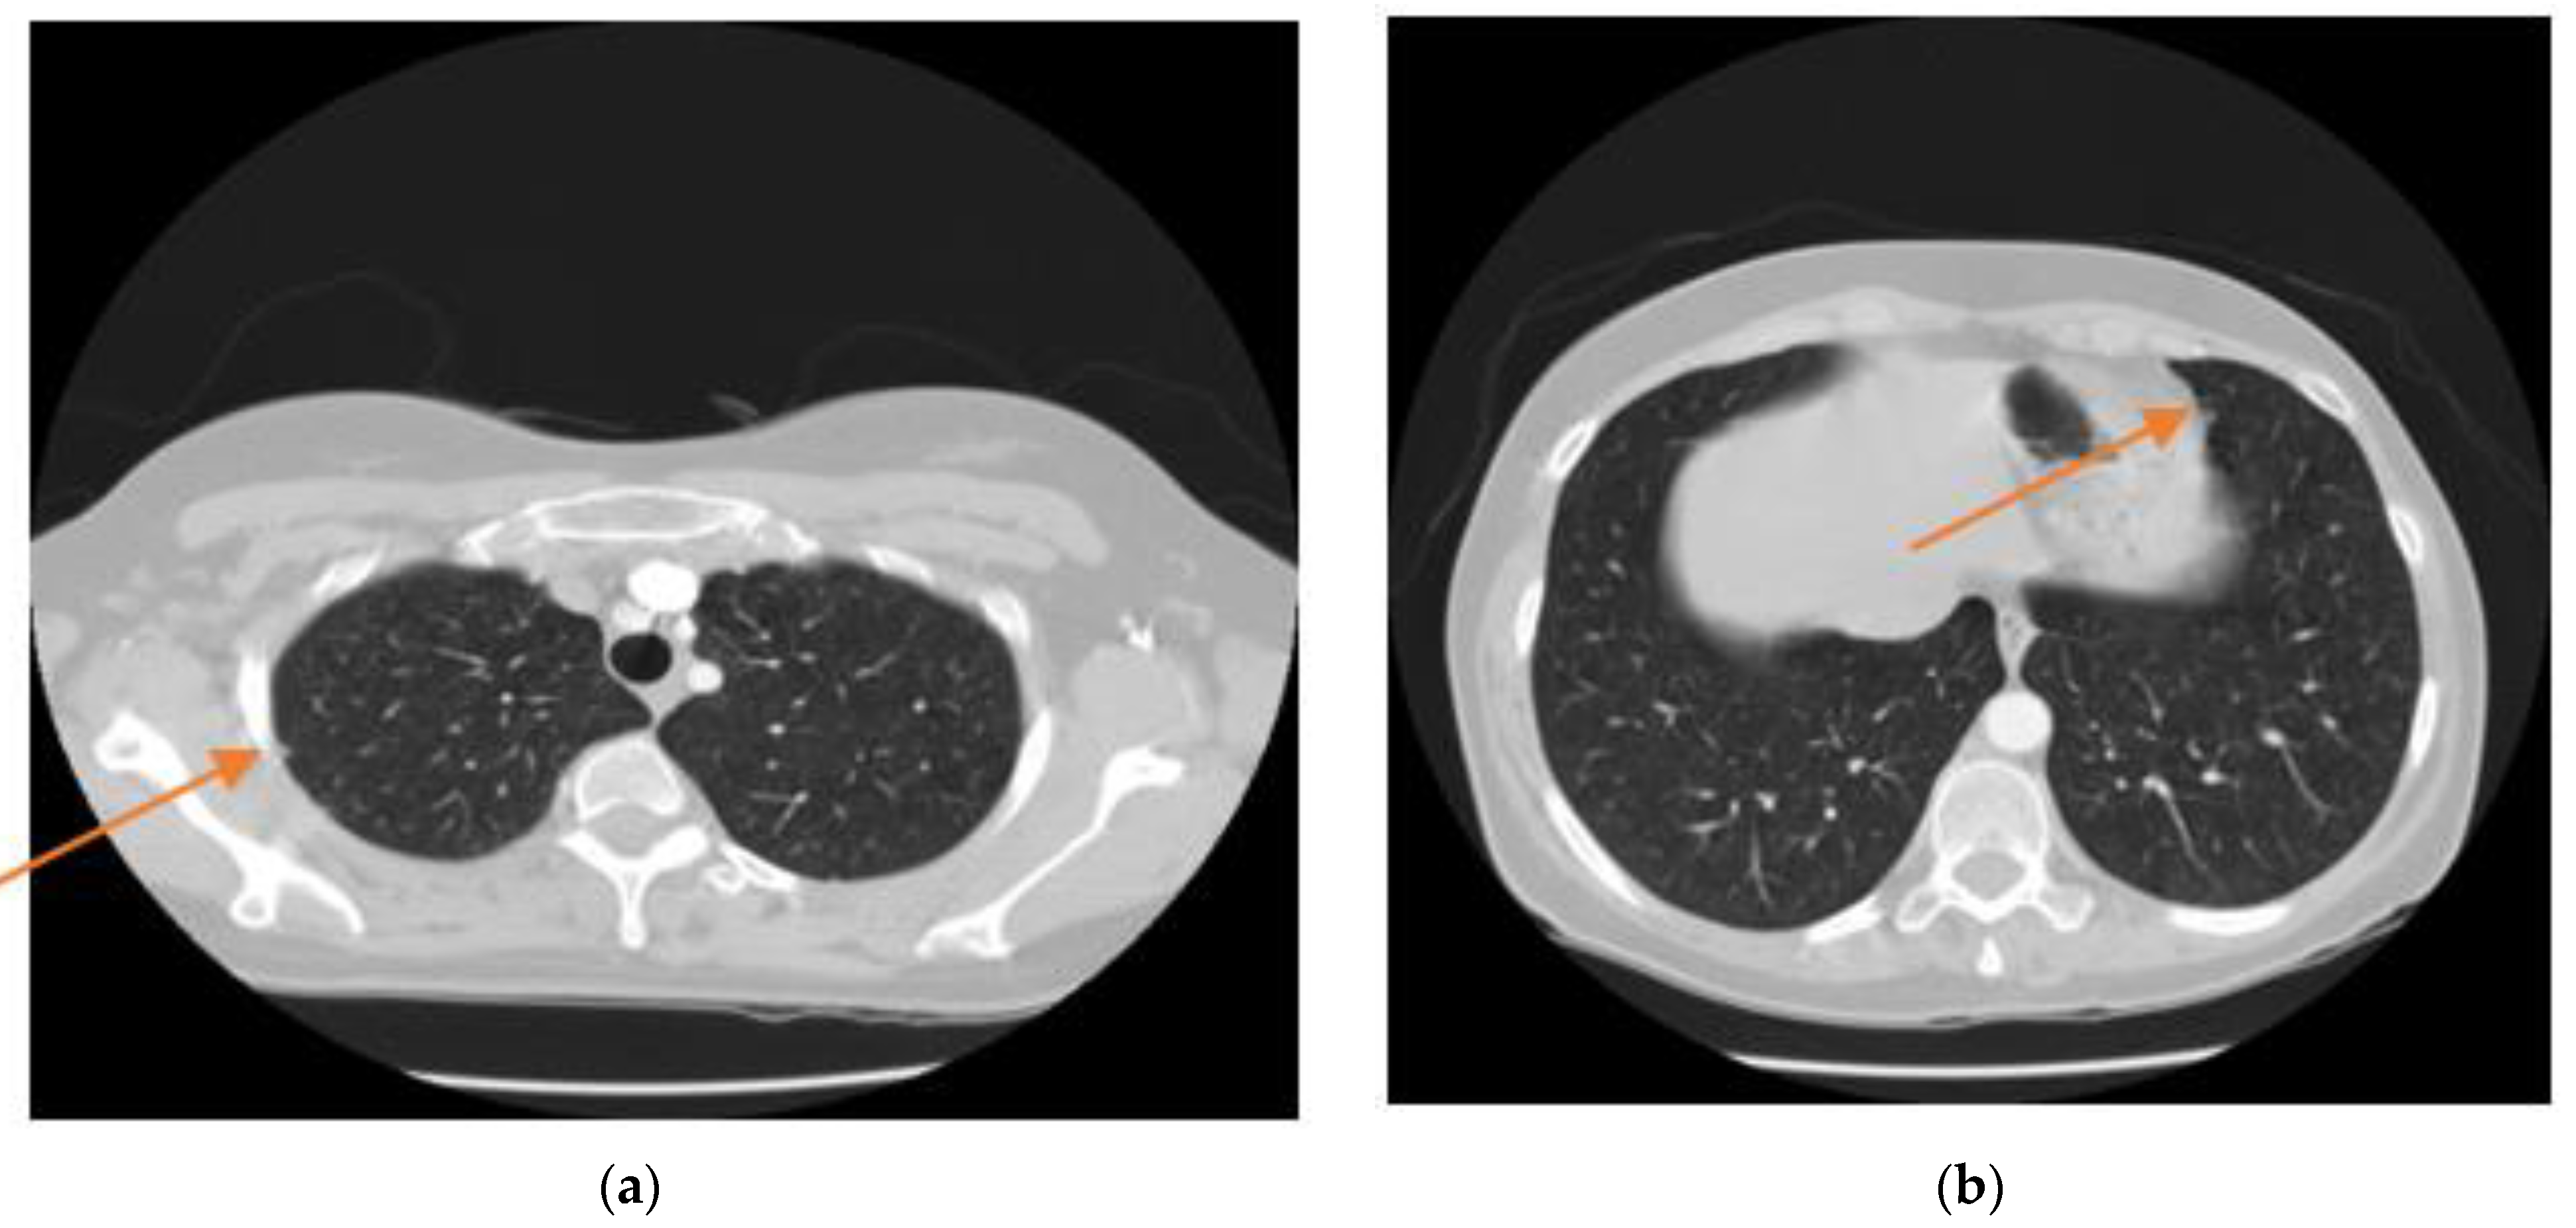

3.1. DICOM Images Reading

3.2. Ground Truth (GT) Extraction

- Removing the blobs connected to the CT image border: To classify the images correctly, the regions connected to the image border are removed, as shown in Figure 4c.

- Labelling the image: Pixel neighbourhoods with the same intensity level can consider being a connected region. When this process is applied to the entire image some connected regions are formed. Figure 4a shows connected regions of integer array of the images that are labelled.

- Keeping the labels with two largest areas: As shown in Figure 5b, labels with the two largest areas (both lungs) are kept whereas the tissues with areas less than the expected lungs are removed.